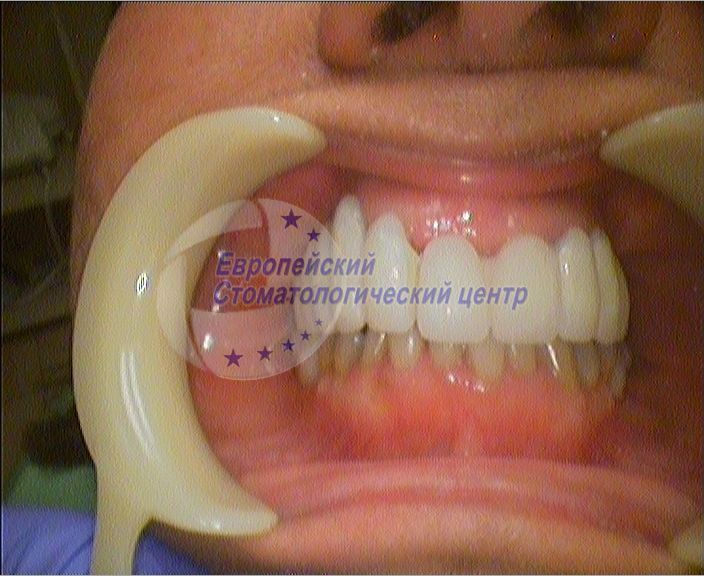

фото через год после операции